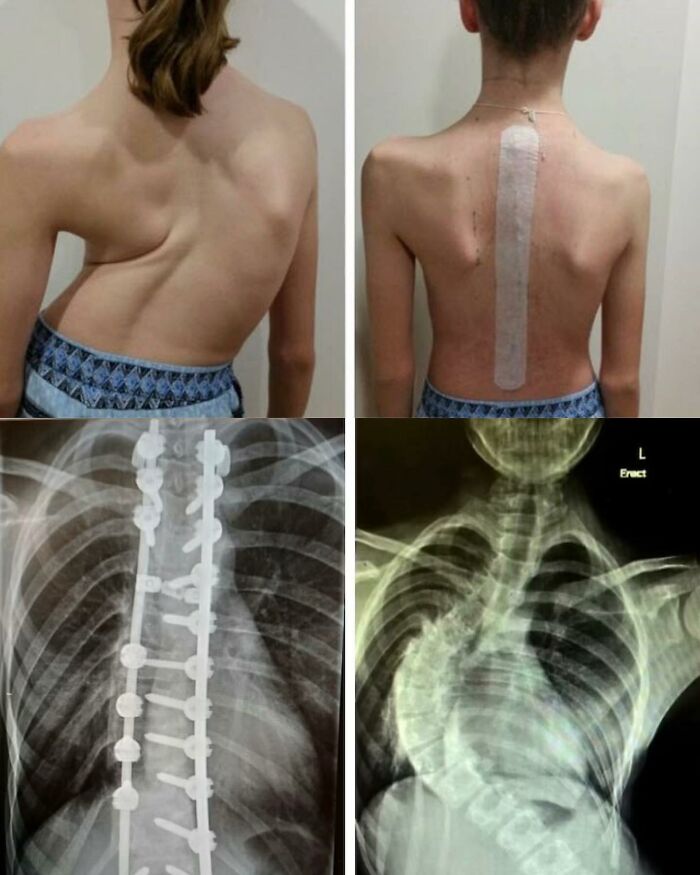

#2 Transforming Curves: From Struggle To Strength – Witness The Journey Of Scoliosis

Scoliosis is characterized by a lateral deviation and rotational deformity of the spine, resulting in an abnormal sideways curvature. It can manifest in different regions of the vertebral column and exhibit varying degrees of severity.

This 13-year-old’s scoliosis was progressing so rapidly that major spinal surgery was her only treatment option. In just over six months, her curve progressed from what was initially 49-degree to a 99-degree curve. The girl now has a combination of titanium rods and screws around her spine. Luckily she fully recovered and got back to her normal activities.

While scoliosis can be caused by conditions such as cerebral palsy and muscular dystrophy, the cause of most scoliosis is unknown. About 3% of adolescents have scoliosis.

Treatment depends on the degree of curve, location, and cause. Minor curves may simply be watched periodically. Management options may involve close observation, utilization of orthotic devices (e.g., braces) for stabilization, or, in severe cases, surgical intervention aimed at rectifying the curvature and achieving spinal stability. The brace must be fitted to the person and used daily until growing stops.

Surgery is usually recommended by orthopedists for curves with a high likelihood of progression (i.e., greater than 45 to 50° of magnitude), curves that would be cosmetically unacceptable as an adult, curves in people with spina bifida and cerebral palsy that interfere with sitting and care, and curves that affect physiological functions such as breathing. To completely straighten a scoliotic spine is usually impossible, but for the most part, significant corrections are achieved.

Credit: Isabel Dayman, Mobile.abc.net.au